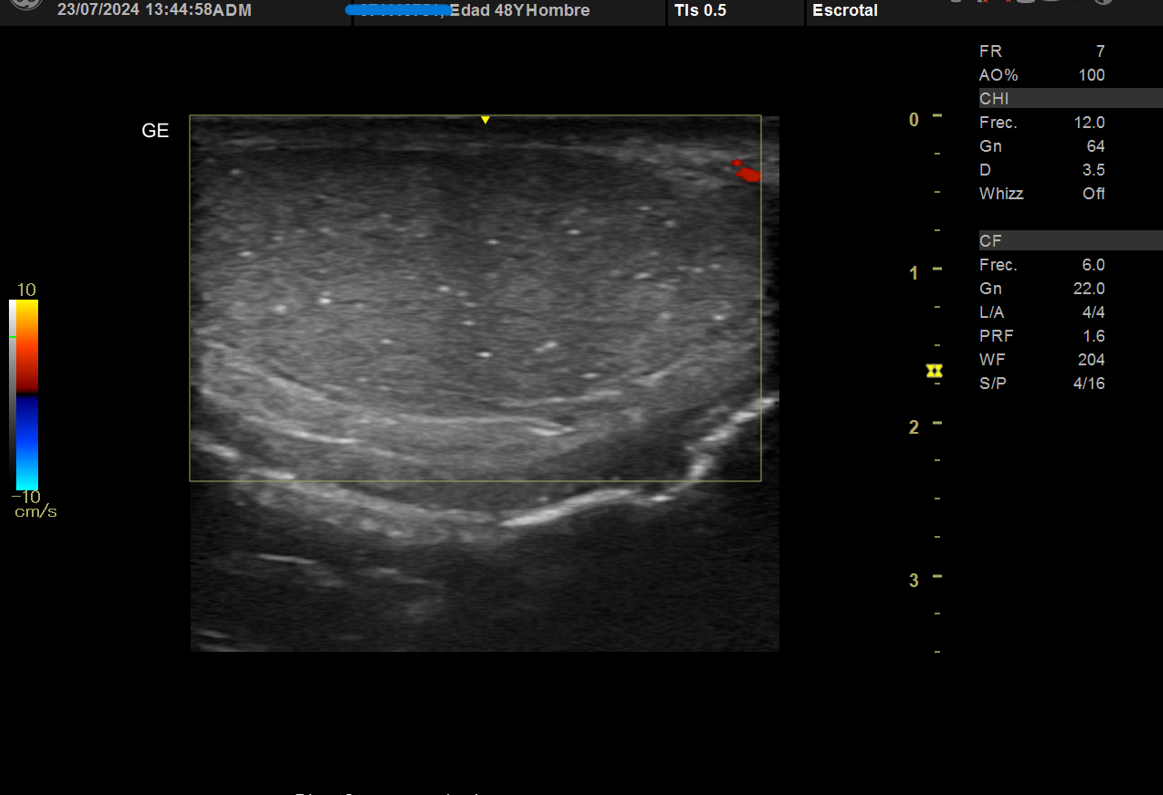

Realizamos ecografía clínica testicular: observamos ambos testículos con microlitiasis bilaterales puntiforme sin sombras acústicasen, en forma de cielo estrellado, vascularización normal, cabeza epidídimo izquierdo con leves signos inflamatorios, mínimo hidrocele.

La ecografía testicular reglada testicular realizada al mes presenta resolución de orquiepidimitis y confirma microlitiasis testiculares.

Inicia tratamiento con cefuroxima 500 mg cada 12 horas, se solicita analítica completa con marcador HCG tumoral y LDH normales, serología hepatitis, sida y sífilis negativa, transaminitis, hemograma normal, cultivo orina positivo a Pseudomonas auriginosa. Ecografía testicular reglada testicular preferente que es realizada al mes con mejoría de orquiepidimitis y confirma microlitiasis testiculares.